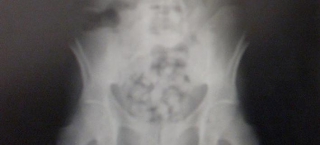

Ενας φρικτός πατέρας στην Κολομβία βρήκε τον πιο απίστευτο τρόπο για να μεταφέρει ναρκωτικά στην Ευρώπη. Ανάγκασε την 11χρονη κόρη του να καταπιεί 104 κάψουλες…